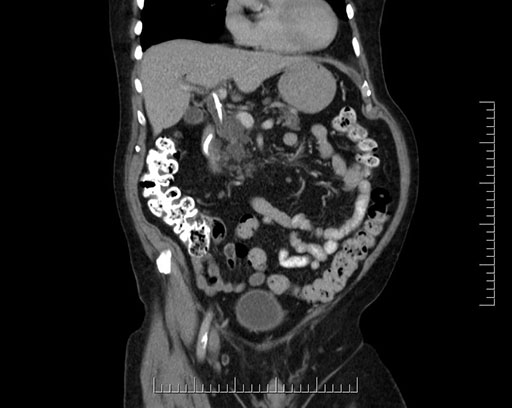

Imaging Analysis

Look through the patient's CT scan to identify any areas of concern for the necessary procedure.

Based on your CT findings, which issue(s) would give reason for "planned slowing down moment(s)" in this case?

Considering a standard Whipple procedure, what step(s) of the operation would you do differently in this case?